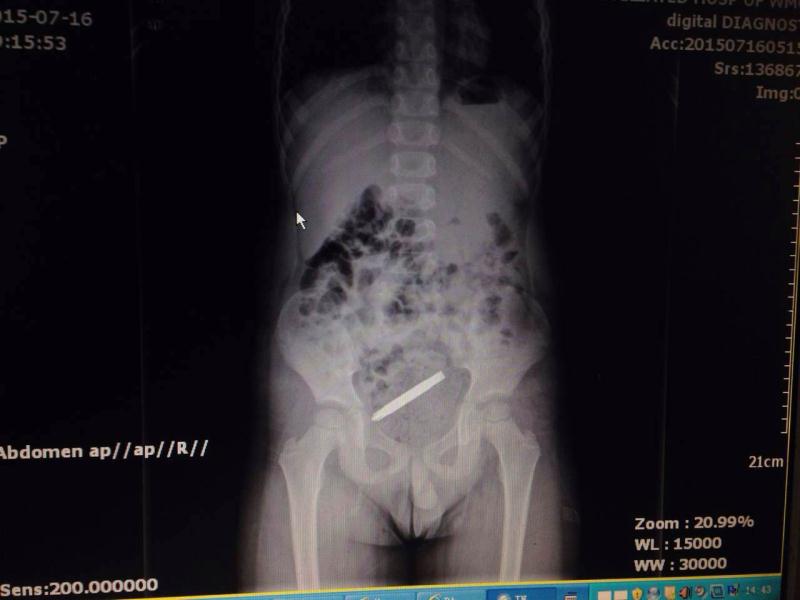

据接诊的陈聪德副主任医师说,他立即给予患儿体检、腹部立位片检查,发现螺丝刀头状金属异物在其胃内,随即邀请儿童消化科会诊,拟予行胃镜检查并取出异物。然而,在此时患儿的症状加重,出现了阵阵腹痛、呻吟不安。由于担心异物伤到消化道壁导致穿孔的可能,再次进行腹部X线拍片检查时发现,该异物竟已进入小肠内。因螺丝刀头一端尖锐,随时有可能穿破肠管。一旦肠穿孔,后果将十分严重。